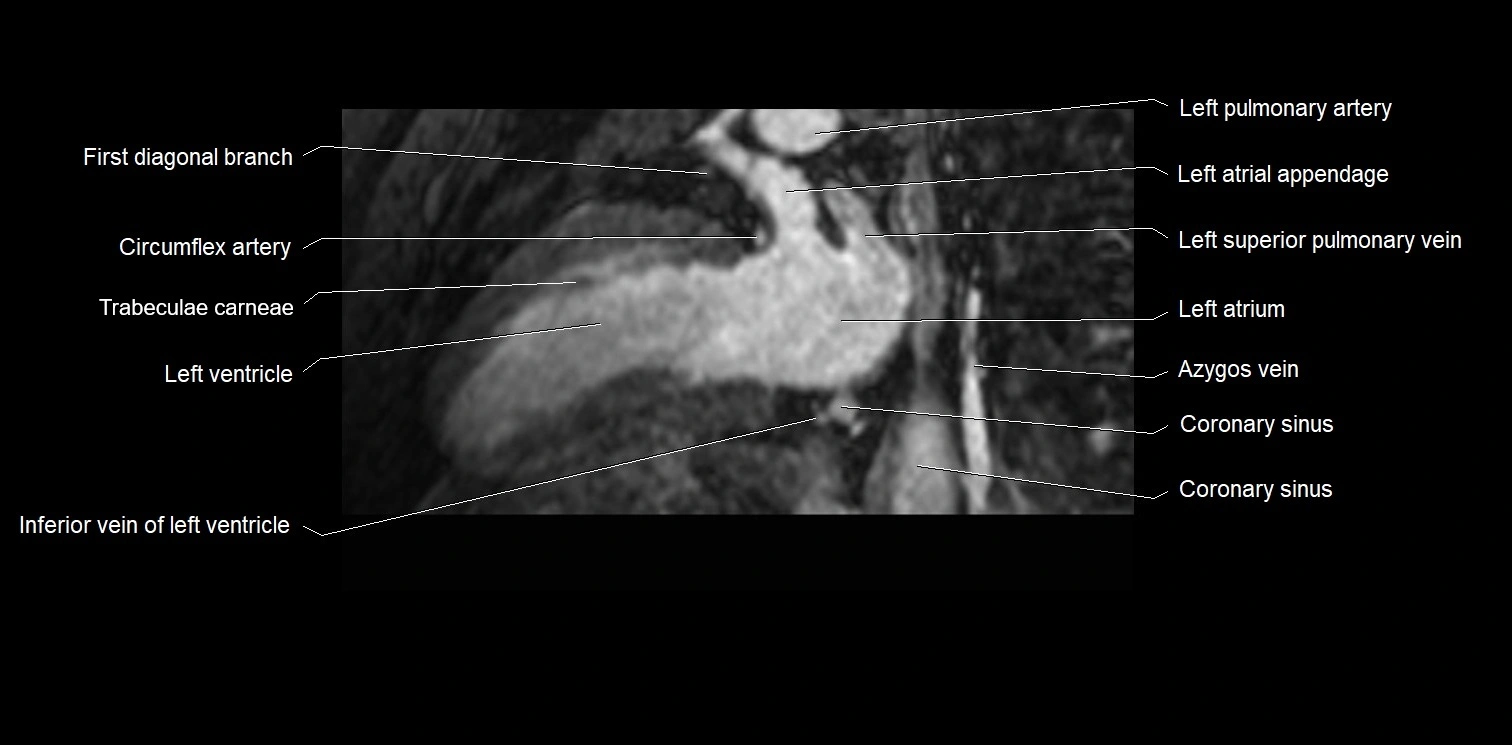

MRI image